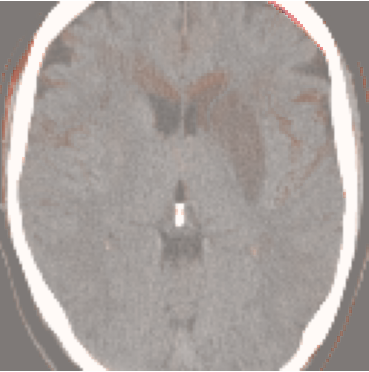

While ACAT revolves around generating counterfactuals, its primary strength lies in accurately identifying pathological regions, which are subsequently employed in a classification pipeline. On the other hand, it falls short in producing credible counterfactual examples, an issue we aim to address in this study. An illustration of this phenomenon is depicted in Figure 2, where we can observe how ACAT is able to generate a saliency map that approximately identifies the pathological region (e, bottom row). However, in the counterfactual example, the lesion remains visible (e, top row). In contrast, our approach not only refines the saliency map but also generates a counterfactual image where the pathology is completely eliminated (f).

4.3 Counterfactual Examples

In Figures 2 and 4 we display examples of healthy images and anomaly maps obtained with the different approaches. We can observe that f-Ano GAN is not able to generate credible counterfactuals and generally produces images of poor quality and unrealistic appearance. On the other hand, the approaches based on diffusion models are able to create more high-quality results. However, the ones obtained with CG and CFG seem to present some artifacts, which may not only impact the realism of the counterfactual examples but also the precision of the anomaly maps obtained from them. In order to better quantify the capability of these methods to accurately segment pathological areas, we compute the Dice scores of the anomaly maps they generate.

We also test our approach on healthy samples. Ideally, we would like our generative process to act as the identity function when given a normal image as input. Some examples are shown in Figure 6, where we can observe that the changes introduced by our sampling technique are relatively minimal and Dif-fuse preserves the structure and general appearance of the images.